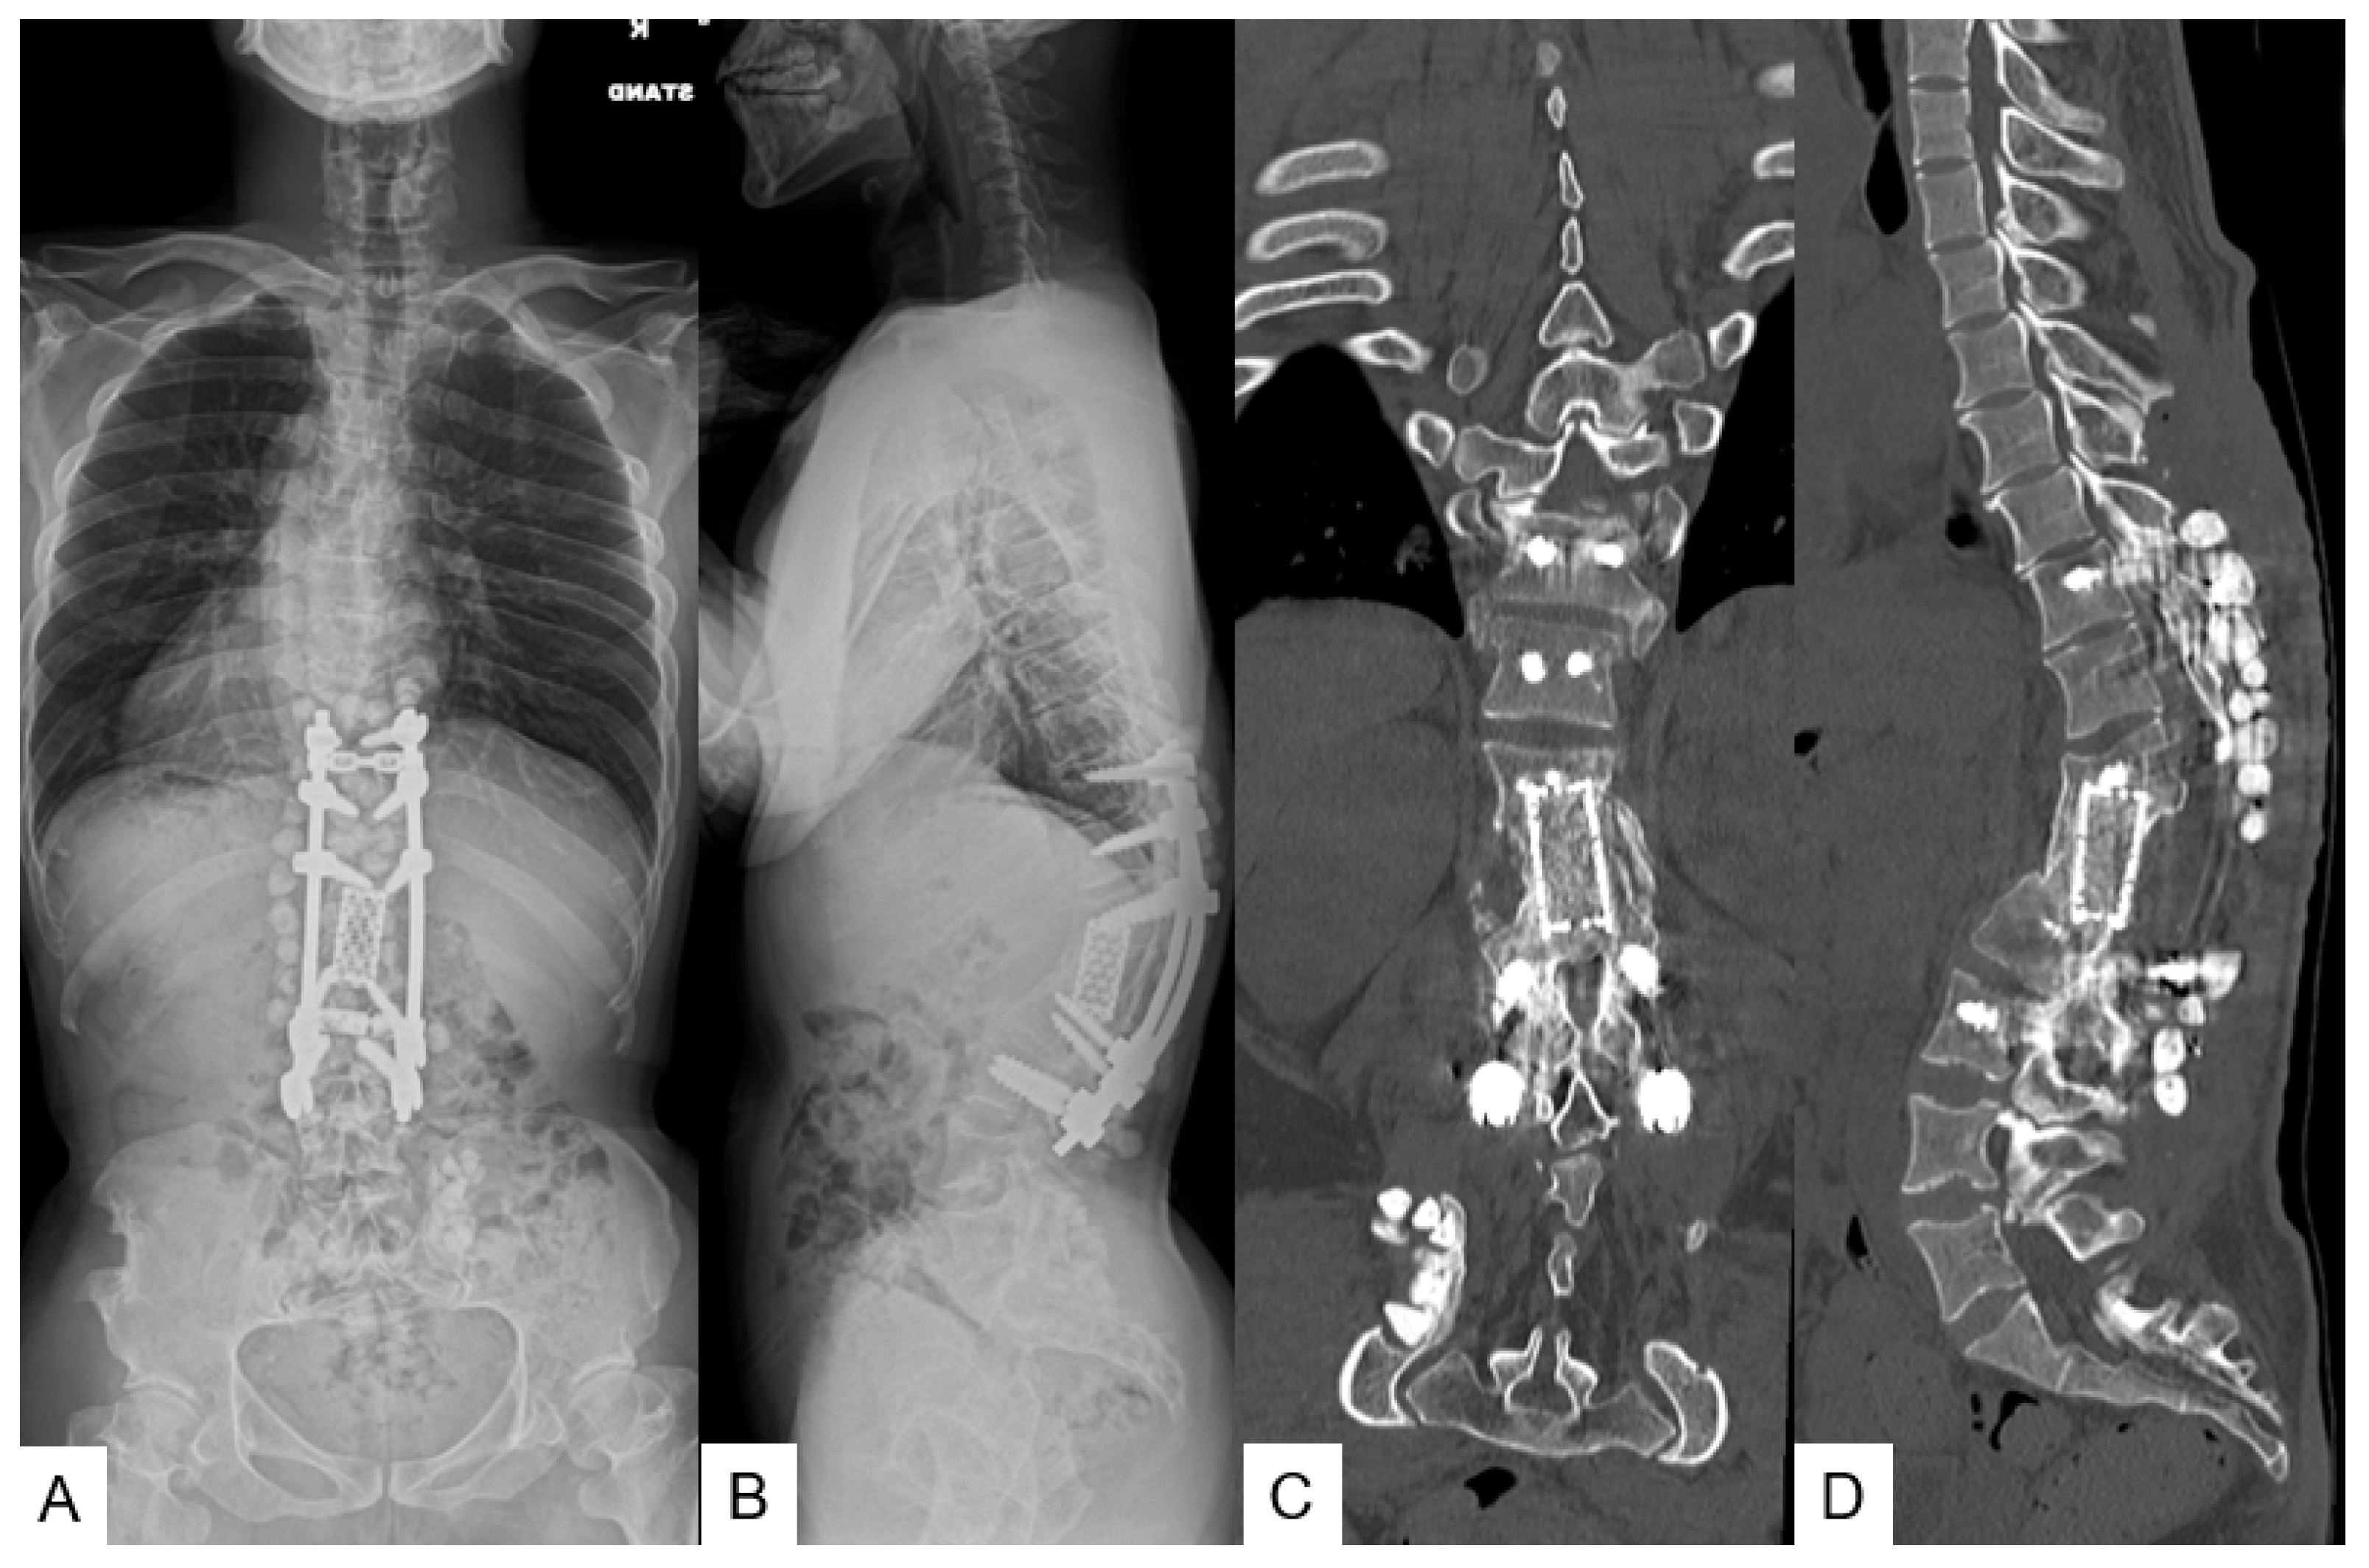

3.1.6. Follow-Up Results